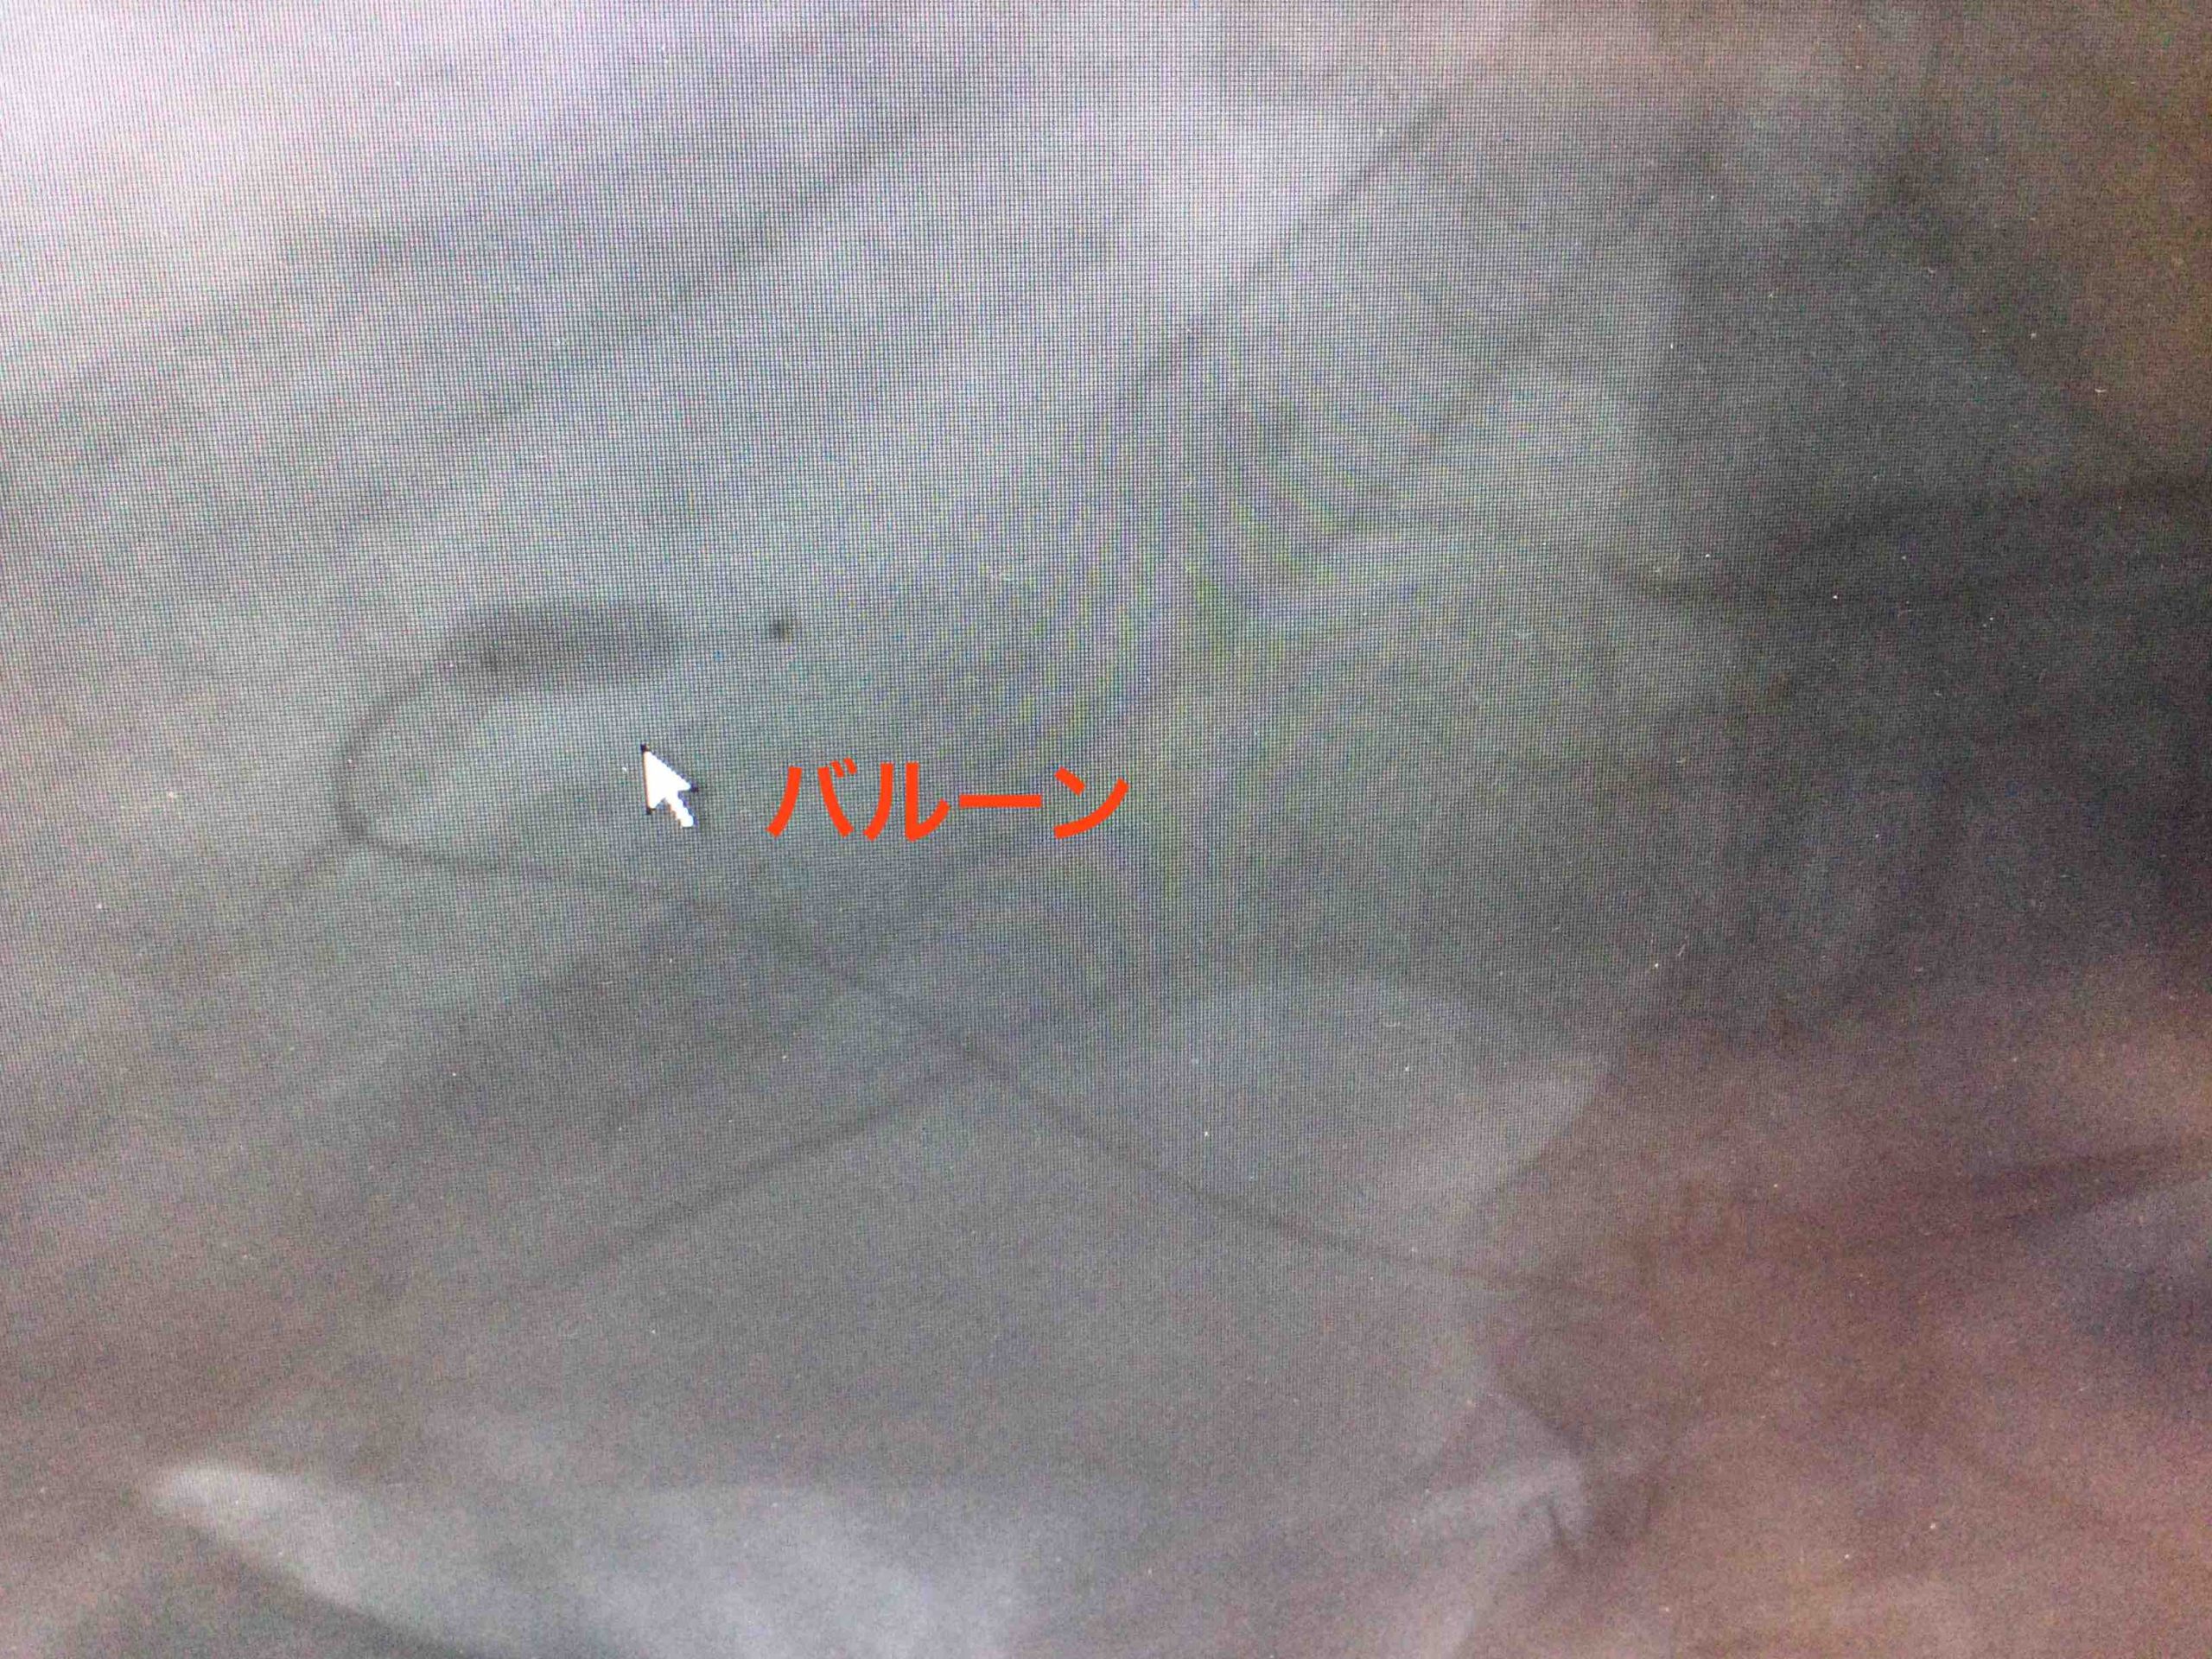

今回の症例では

バルーン付きカテーテルを用いた

手術になりました。

バルーん

肝臓がんを栄養する

動脈血流の勢いが良すぎると

お薬をカテーテルに入れた際、

目的の腫瘍にとどまらず

効果が弱くなる場合があります。

そこで、

バルーンを膨らますことにより

血流がゆっくりになり

腫瘍にお薬がたくさん入りやすくなる

という場合に用いられます。